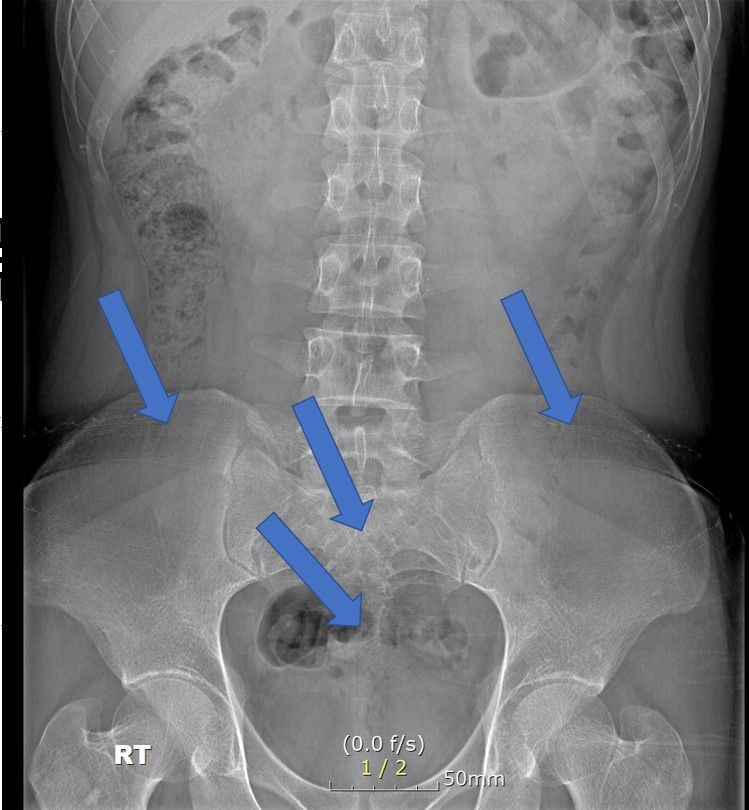

심할때는 1시간 걷다가 갑자기 골반과 옆구리가 알배기는듯이? 근육통이 심한듯이 느낌이와서 잠시 앉아서 쉬었습니다. ct영상으로도 디스크로 때문에 아프기엔 정상적인 정도라 하셔서 왜 아픈지 모르겠네요 . 현재 옆구리 좌,우 ,골반뒤쪽과 천추 꼬리뼈 또한 통증이 있으며 자고 일어나면 통증이 시작되고있습니다. 무엇때문인지 답답합니다. CT또한 촬영 했습니다.

x ray에 통증있는부분 표시 했습니다. 주로 뒤쪽으로 아픕니다. 3개월 됬습니다...직업상 앉아있는시간이 많습니다.